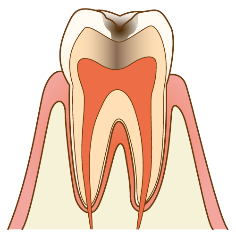

C2

むし歯菌がエナメル質より深く象牙質まで進行しているが歯の神経までは達していないむし歯。

治療:むし歯菌に感染した歯質を取った後、むし歯の範囲や部位に応じた適切な材料を使って修復します。